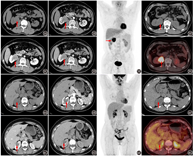

患者女,42岁,体格检查发现右肾肿物2周,腹部增强CT可见右肾前唇外突性肿块,大小为3.4 cm×3.3 cm×3.0 cm,增强扫描皮质期明显强化,实质期及排泄期强化低于肾实质(图2A,图2B,图2C,图2D)。患者进一步行18F-FDG PET/CT显像,见右肾中部前唇占位,显像剂摄取同周围肾实质相当,SUVmax 2.6(图2E,图2F,图2G)。